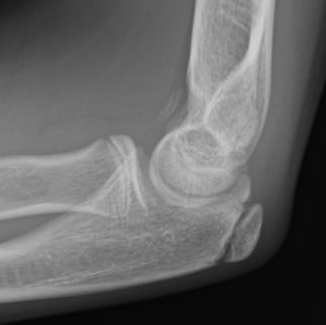

Multiple elbow loose bodies

Single loose body in adolescent

Capitellar OCD www.boneschool.com/capitellar-OCD

Elbow osteoarthritis and & stiffness www.boneschool.com/elbow-OA